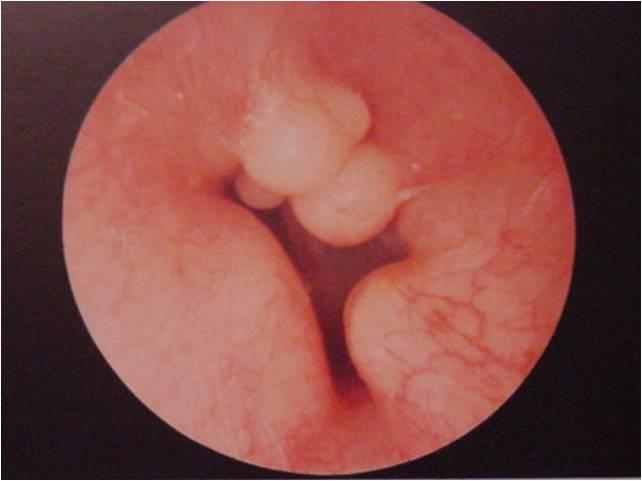

Exostose du conduit auditif

L’exostose correspond à la formation d’os dans le conduit auditif externe. C’est une réaction de défense de l’organisme contre une agression extérieure. Cette affection est la conséquence de l’agression de l’eau froide sur le conduit auditif externe. Les surfeurs mais aussi les kayakistes et les nageurs en eaux froides comme les triathlètes y sont sujets.

Les conséquences peuvent être graves. L’exostose peut en effet provoquer une mauvaise évacuation de l’eau entre la masse osseuse et le tympan. D’où un risque d’otites externes extrêmement douloureuses à répétition. Et à long terme, si rien n’est fait, les excroissances osseuses peuvent aller jusqu’à l’obturation complète et la perte d’audition.